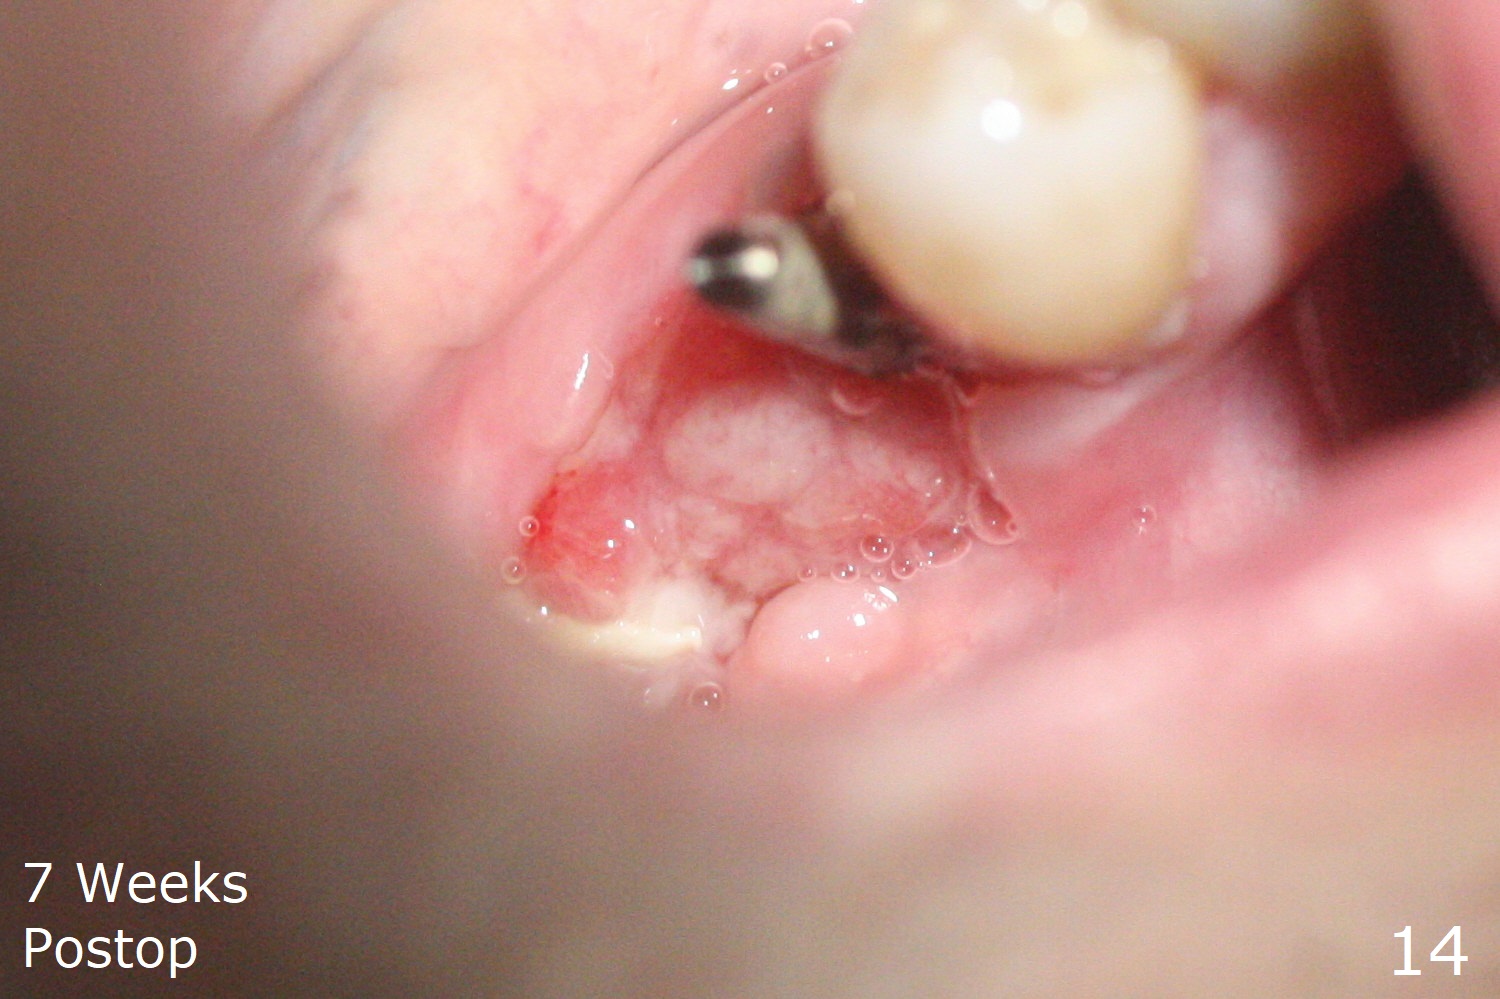

The implant at #30 was also buccally placed (Fig.6,7) and should be corrected in the same manner (Fig.7 green). Due to the bone being harder in the molar region, a smaller and shorter implant (4x11 mm vs. 5x13 mm) shifts slightly buccally while being placed (Fig.8,9). Since primary stability is lower (<20 Ncm vs. 35 Ncm associated with the implant #29), an abutment is not placed, which may be favorable to healing, but it is difficult to achieve primary closure. After bone graft (Fig.9 *) and 2 layers of PRF, Cytoplast is placed. Cytoplast appears to be exposed buccally (Fig.10 <) and occlusally (Fig.11 ^) asymptomatic 9 days postop. Exposure of Cytoplast is more distinct without sign of infection 15 days postop (Fig.12). The patient returns with chief complaint of "foul smell" 7 weeks postop (coronavirus lockdown). Although the Cytoplast exposes more (Fig.13 (* exposed; @ unexposed)), the underlying gingiva remains healthy (Fig.14). While the bone height decreases at #29, the bone density at #30 increases 4.5 months postop (Fig.15). The gingiva heals. The implant at #30 is uncovered 6 months postop. The lingual plate has to be removed for the uncover, while the coronal end of the buccal one is missing. No bone graft is added. When the 4.5x4 mm healing abutment is removed 6.5 months postop, the buccal plate looks concave at #30 (Fig.16' *). The buccal plate looks thin at #29 with a cotton roll placed buccally (Fig.16 R). The lingual plate at #29 is coronal to the buccal one (Fig.17). The buccal gingiva at #29 is quite long (Fig.18). The coronal buccal plate appears to be missing (Fig.19 >), which will be watched. A 4.5x7.5(4) mm cemented abutment is torqued (Fig.20).